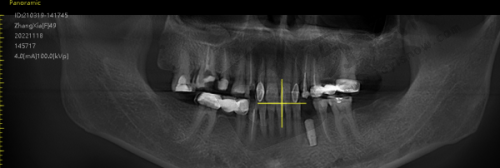

徐秋霞医生在牙齿矫正、种植牙、美学种植、全口义齿、局部义齿等领域有着丰富的临床经验。在牙齿矫正方面,她能够精细分析患者牙齿的状况,制定个性化的矫正方案,帮助众多患者拥有整齐美观的牙齿。对于种植牙和美学种植,她凭借不错的技术,确保种植体的稳固和美观,修复患者的咀嚼功能。在全口义齿和局部义齿修复上,也能根据患者口腔条件,打造出舒适、贴合的义齿,深受患者的信赖和好评。

徐秋霞医生具备专精的执业资格和相关资质。她是北京玮杰口腔诊所的主治医师,经过多年的专精学习和临床实践,积累了丰富的口腔医疗经验。她拥有国内认可的口腔医学专精执业证书,这是她具备合法行医资格的重要证明。同时,她不断学习和掌握全新的口腔医疗技术和理念,能够为患者提供高质量的口腔诊疗服务,其专精能力和资质是值得患者信赖的。